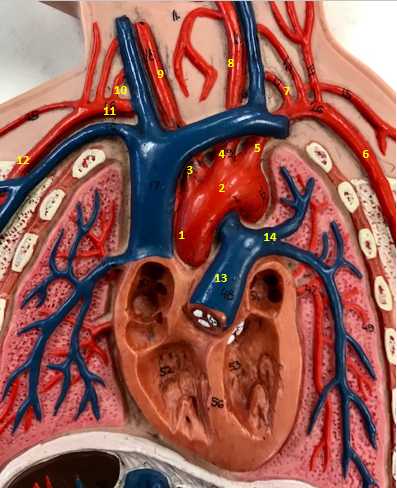

Aorta

Name #2

Brings blood out of left ventricle

Function of aorta

Brachiocephalic artery

Name #3

Supplies oxygenated blood to right arm shoulder neck and head

Function of brachiocephalic artery

Left common carotid artery

Name #4

Supplies oxygenated blood to left neck and head

Function of left common carotid artery

Left subclavian artery

Name #5

Supplies oxygenated blood to left arm shoulder

Function of left subclavian artery

Left axillery artery

Name #6

supplies blood to left armpit and upper limb

Function left axillary artery (6)

Left vertebral artery

Name #7

Supplies blood to brain and spinal cord

Function of left vertebral artery (7)

Left common carotid artery

Name #8

Supplies blood to left neck and head

Function of left common carotid artery (8)

Right common carotid artery

Name #9

Supplies oxygenated blood to right neck and head

Function of right common carotid artery (9)

Right vertebral artery

Name #10

Supplies blood to brain and spinal cord

Function of right vertebral artery (10)

Right subclavian artery

Name #11

Supplies blood to right arm and shoulder

Function of right subclavian artery

Right axillery artery

Name #12

Supplies blood to right armpit and upper limb

Function of right axillery artery (12)

Pulmonary trunk

Name #13

Bring blood out of right ventricle to lungs

Function of pulmonary trunk (13)

Left pulmonary artery

Name #14

Bring blood to left lung

Function of left pulmonary artery (14)